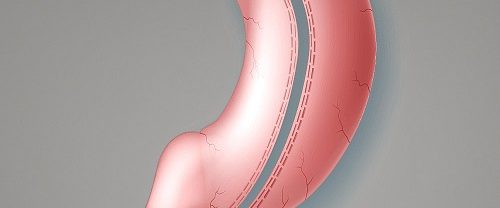

Tüp Mide Ameliyatı Nedir? Tüp mide ameliyatı, obezite problemi yaşayan bireylerde kilo kaybını desteklemek için uygulanan cerrahi bir prosedürdür. Bu operasyon, mideyi küçülterek ve sindirim sistemini değiştirerek kişinin daha az yemek yemesini ve dolayısıyla kilo vermesini sağlar. Bu ameliyat, genellikle kilo verme çabalarıyla sonuç alınamayan veya obeziteye bağlı sağlık sorunları yaşayan kişiler için bir seçenek…